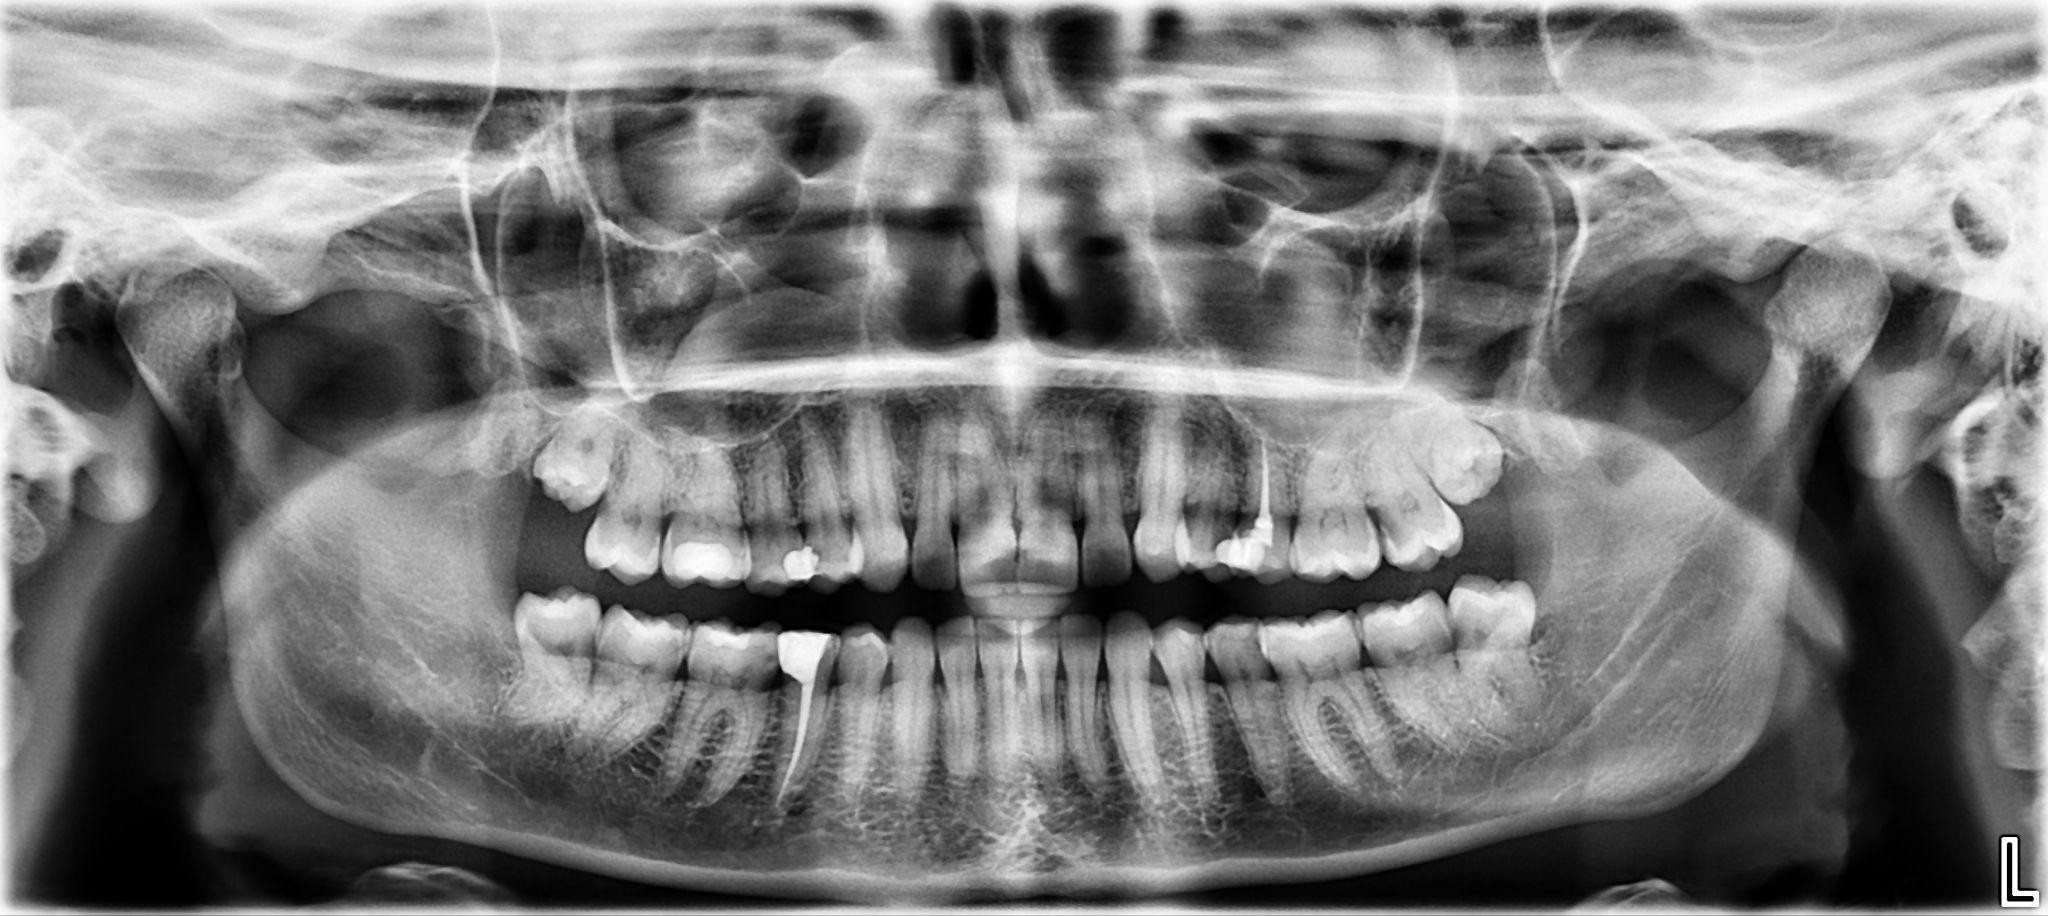

9. What options can be selected for the first quadrant of this panoramic X ray?

10 / 24

10. What options can be selected for the second quadrant of this panoramic X ray?

11 / 24

11. What options can be selected for the third quadrant of this panoramic X ray?

12 / 24

12. What options can be selected for the forth quadrant of this panoramic X ray?

13 / 24

13. What options cannot be selected for the first quadrant of this panoramic X ray?

14 / 24

14. What options cannot be selected for the second quadrant of this panoramic X ray?

15 / 24

15. What options cannot be selected for the third quadrant of this panoramic X ray?

16 / 24

16. What options can be selected for the forth quadrant of this panoramic X ray?